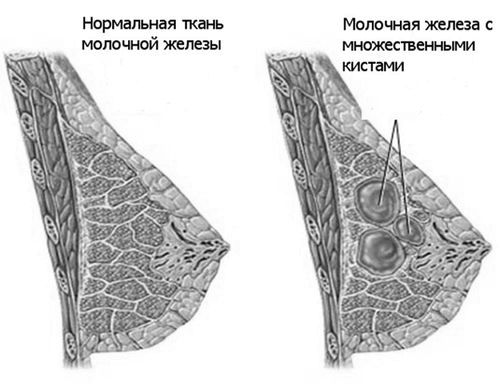

Розростання клітин епітелію залозистої тканини молочної залози називається гіперплазією. Якщо при діагностиці виявляється переважання саме гіперплазії часточок, то таку форму мастопатії називають аденозом.

Він може зачіпати окремі часточки і охоплювати всі груди цілком, вражати одну молочну залозу або обидва органи відразу.

- Далі жінка може відчути появу ущільнень у молочній залозі. Вони можуть прощупується як окремі ущільнення, якщо зачеплена одна або кілька часточок органу, або як масивне дископодібне освіту, якщо порушена вся груди.

- На відміну від онкологічних пухлин, у доброякісного Аденоз повинні бути гладкі і рівні краї утворень. Можуть з'явитися виділення із сосків, зміна обсягів і форми грудей.

- Локальний, що має дольчатое будова з навколишнього його капсулою з фіброзної тканини.

- Вогнищевий, що представляє собою одне або кілька рухомих щільних утворень. Має сприятливий прогноз і не позначається істотно на функції органу, але здатний викликати асиметрію грудей.

- Дифузний, який охоплює всю железистую тканину і може вражати протоки, що призводить до порушення функції органу і часто стає причиною утворення внутрішньопротокових папілом.